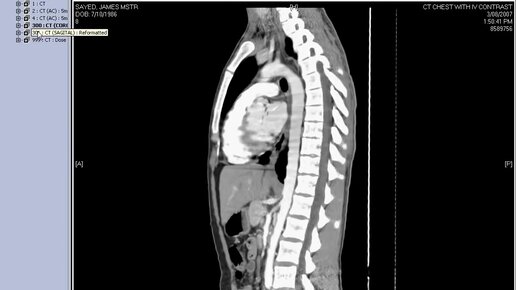

Что видно на КТ грудной клетки (видео)